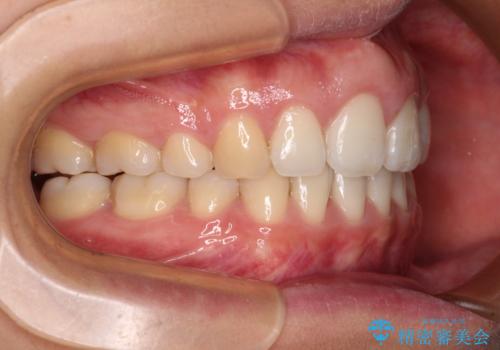

- 前歯の出っ歯と口元の閉じにくさを気にして来院された患者様です。

口元を積極的に引っ込めるために、上下左右の小臼歯4本を抜歯することとしました。

4本の歯を抜歯したことで、飛び出していた口元が引っ込み、横顔が大きく改善されました。

咬み合わせが悪化することのないようにスペースを閉じていくことができ、比較的スムーズに治療を進めることができました。